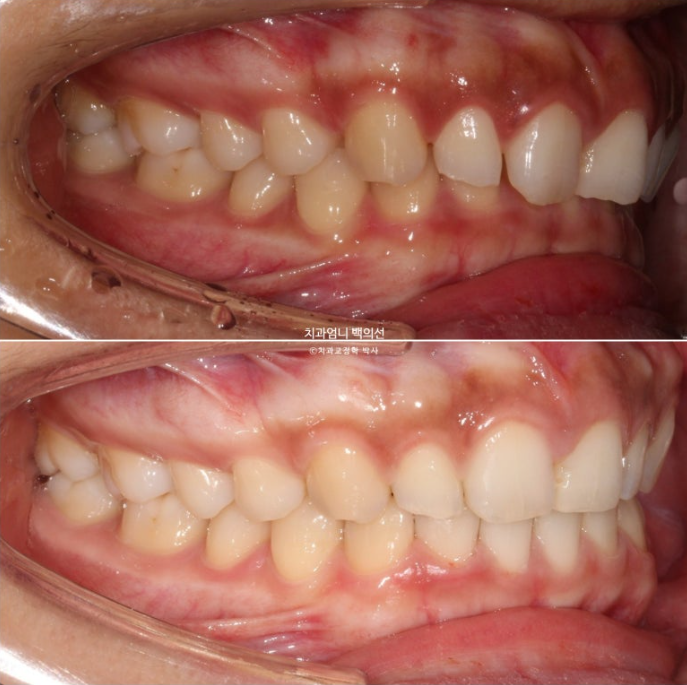

어금니교합은 좋습니다.

어금니 교합이 좋아 인비절라인 라이트 권유드렸고, 대신 미니스크류를 심고 고무줄을 걸어 길지 않은 기간에 과개교합과 거미스마일을 확실히 개선하기로 했습니다.

좋았던 교합은 잘 유지되었고

과개교합의 확실한 개선

앞니가 뒤로 쓰러져 있던 옥니도 상당히 개선되었습니다.

아래앞니과 위 앞니의 상당량의 함입이 눈에 띕니다. 위아래 앞니가 2mm씩 함입되었습니다.

덕분에 입술은 처음보다 좀 더 편하게 다물리게 되었습니다.